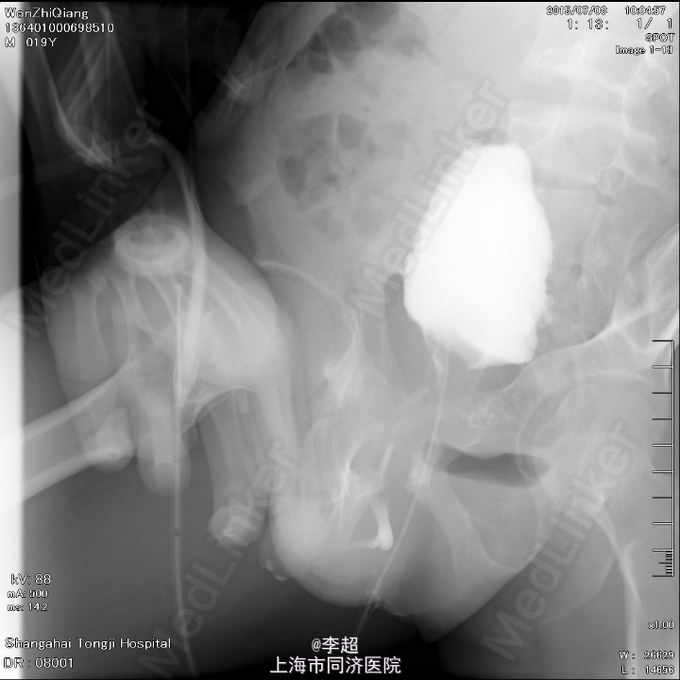

查体 辅查

患者尿道开口于阴囊下,会阴部,无法控尿,尿液自行流出 尿道造影仅显示假道,正常尿道仅存留阴茎短尿道,约5cm长

择期行耻骨下缘切除+阴囊皮瓣代尿道成形+尿道膀胱拖入术 手术过程:行会阴部倒Y形切口切口,切口包括会阴部尿道造口处,术中见阴茎部尿道存在尿道-阴茎皮肤瘘道,予切除瘘道。分离后尿道,探查见后尿道疤痕明显,并且于耻骨相连,局部粘连严重。考虑有假道存在可能,遂做耻骨上纵行切口4cm,探查膀胱发现距目前尿道口处1cm处前方存在另一内口,为盲道,盲端被变形耻骨完全遮挡。遂使用骨刀劈凿穿耻骨并切除耻骨下缘,凿通至膀胱盲道,将盲端断断显露,使用膀胱镜探查盲道,见盲端口膀胱肌肉括约功能较好,推断为真性尿道,使用左侧阴囊及大腿根部皮瓣约8cm*3cm大小,分离皮瓣下组织血管形成血管蒂,翻转皮瓣形成尿道,将皮瓣尿道近端拖入膀胱,与真性尿道膀胱黏膜处直针缝合。另将皮瓣尿道远端与阴茎部正常尿道粘膜缝合,留置F14号导尿管,假道处尿道予留置Foley14导尿管。